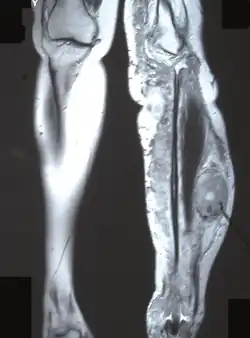

Для данного заболевания характерно появление большого количества нейрофибром, как кожных, так и плексиформных. Кожные нейрофибромы представлены небольшими доброкачественными и ограниченными новообразованиями. Они располагаются подкожно, растут на оболочках мелких нервов кожи. Плексиформные нейрофибромы развиваются на крупных нервах и приводят к нарушению их функций[26]. Также плексиформные нейрофибромы характеризуются своими большими размерами. Встречаются у 30 % больных нейрофиброматозом I типа[22].

Длинные трубчатые кости могут быть атрофичными, изогнутыми, иногда же, наоборот, гипертрофированными, утолщёнными. Компактное вещество в гипертрофированной кости утолщено. На поверхности кости видны периостальные гребни, иногда обнаруживаются и параостальные окостенения. Внутрикостные нейрофибромы в трубчатых костях выглядят как ограниченные вздутия и кистовидные образования[36].